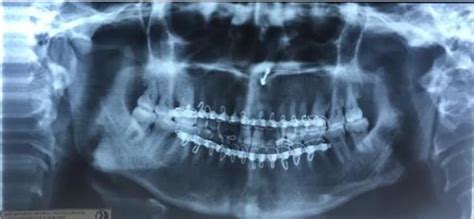

Tmj Radiographic Features

Panoramic Radiograph TMJ